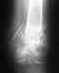

Абстрактно говоря, пожилым людям с переломами шейки бедра обычно делается эндопротезирование. Возможность операции определяется не возрастом как цифрой, а уровнем активности пациентки до этой травмы и общим состоянием ее здоровья, т.е. функцией основных систем и органов. Никаких даже намеков об этих аспектах нет.

Без операции шансов на сращение нет. Нужно в любом случае активизировать пациентку, пусть ходит с костылями или ходунками. На поврежденную ногу можно наступать, сколько получается.